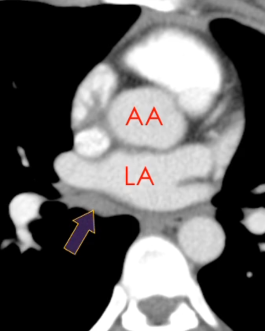

Récessus Aortique supérieur

Sinus Oblique

Sinus Veineux Pulmonaire